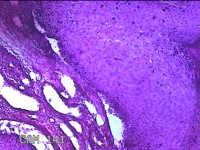

额部肿物

性别

女

年龄

32岁

临床诊断

寻常疣

一般病史

额部起疹1年,不痒。

标本名称

大体所见

灰白暗红色肿物0.7x0.5x0.2cm一个,表面光滑,切开肿物呈实性,切面灰白粉红色,质软。

图3